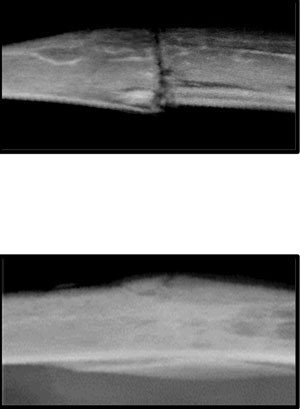

Two bone xrays. Top xray shows an old bone with more texture, indicating deposits of weak fibrotic tissue. bottom image shows a young bone with much less texture.

Top slide illustrates an older bone, where fracture repair is slower and can lead to deposits of weak fibrotic tissue. Bottom slide shows rejuvenated fracture repair from exposure to a youthful circulation; the rate and amount of bone tissue deposited is enhanced.